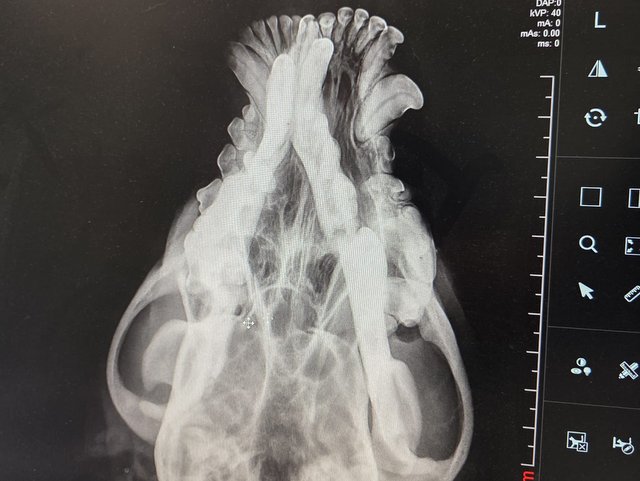

Röntgenbilder zeigten das Ausmaß der Zerstörung des Unterkiefers und den Bruch eines Beines.

Dieser Hund muss grausame Schmerzen haben, Zähne sind aus der Verankerung gerissen und sein Gesichtsschädel ist nicht mehr symmetrisch. Ein großes Stück des Unterkiefers ist komplett abgebrochen.

Es braucht sicher viel Geschick, um das wieder so zusammenzusetzen, dass der Hund später problemlos fressen kann.